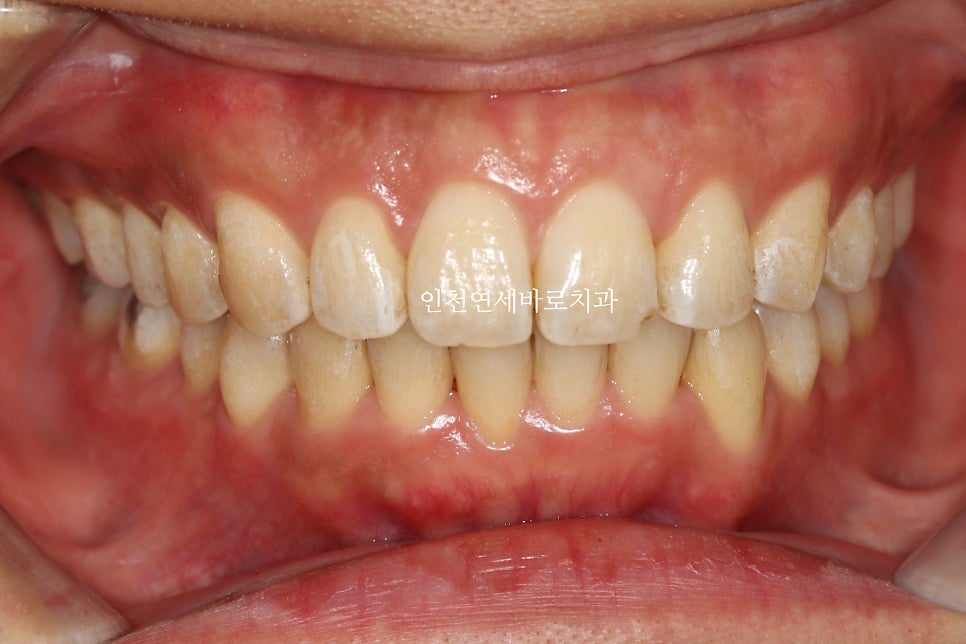

앞니가 뻗쳐있고, 아래치아가 안보이고

덧니가 심해서 내원한 환자분입니다

치료 전과 후의 비교입니다.

교합도 양호하게 마무리.